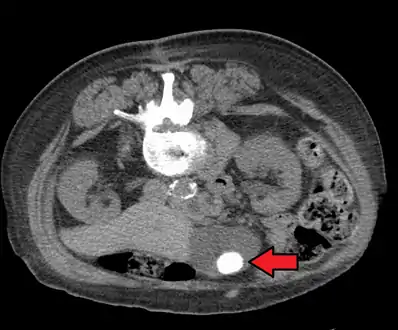

Diagnosis is typically confirmed by abdominal ultrasound. Other imaging techniques used are ERCP and MRCP. Gallstone complications may be detected on blood tests.[2]

Large gallstone as seen on CT- A normal gallbladder on ultrasound with bowel peristalsis creating the false appearance of stones